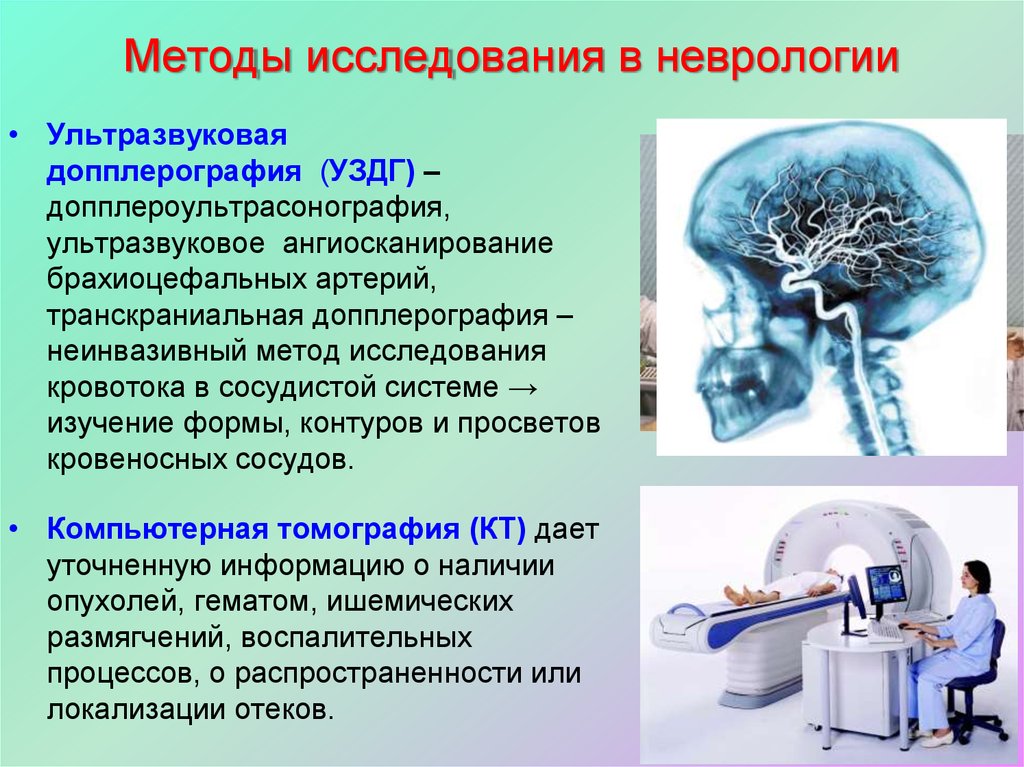

Компьютерная томография в неврологии презентация - 86 фото